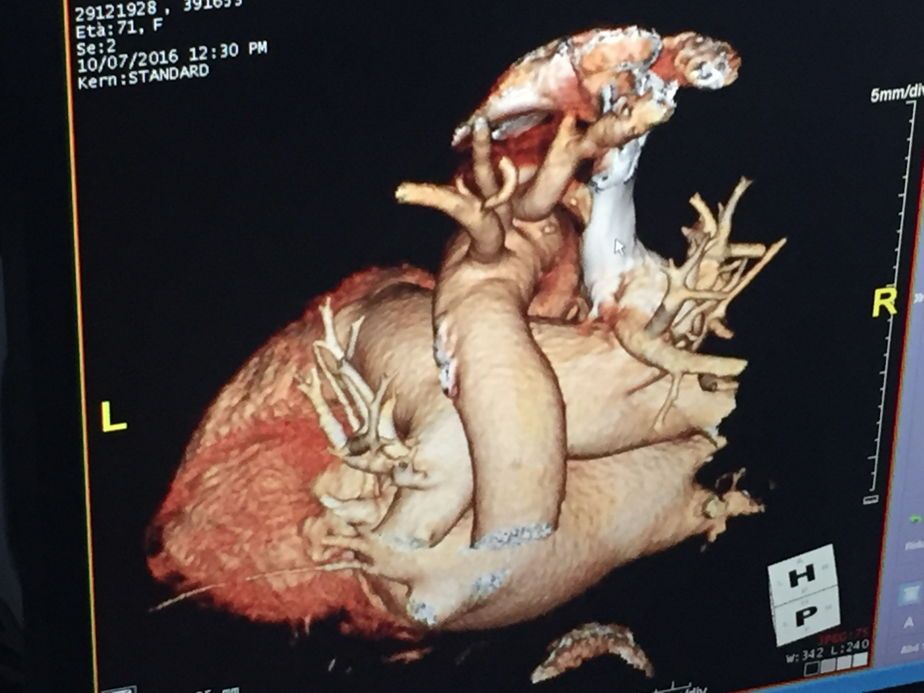

LIBERO PROFESSIONISTA con esperienza ventennale maturata presso il Policlinico Gemelli di Roma dove ha ricoperto negli anni il ruolo di assistente medico presso le diverse unità operative acquisendo esperienza nelle diverse branche della cardiologia clinica e strumentale ed in particolare dal 2012 al 2020 cardiologo nell’unita’ operativa complessa di Cardiochirurgia del Policlinico Gemelli diretta dal prof. Massimo Massetti (volume del centro di 800 interventi al cuore all’anno con particolare attenzione alla chirurgia mininvasiva ed alla riparazione valvolare). Dal 2017 incarico professionale di alta specializzazione come responsabile del programma di imaging ecocardiografico avanzato presso la stessa unità operativa complessa di Cardiochirurgia. Esperto di ecocardiografia 2D e 3D in particolare nello studio di cardiopatie complesse, valvulopatie, plastiche riparative valvolari, chirurgia mininvasiva, TAVI, MITRACLIP, PFO, TIARA, cardiopatia ischemica, scompenso cardiaco, cuori artificiali, sala ibrida, sala emodinamica. Professore di Ecocardiografia presso l’Universita’ Cattolica del Sacro Cuore di Roma al Master di primo livello in Tecniche di Ecocardiografia ed al Corso di laurea triennale in Fisiopatologia Cardiocircolatoria e Tecniche di Perfusione Cardiovascolare.

Foto e video